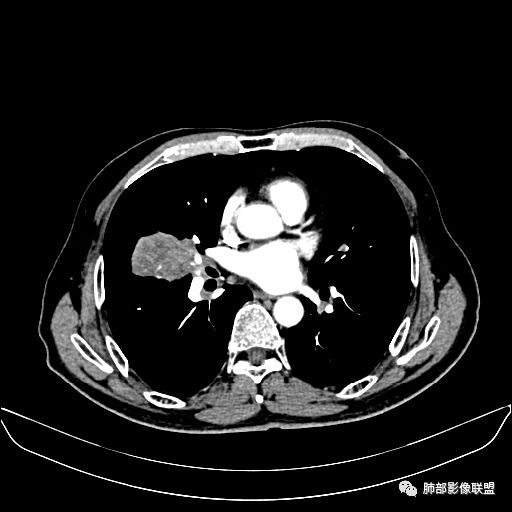

住院4天后行胸部增强CT

动脉期

老年男性,因“咳嗽咳痰1月余。”入院。病程中咳嗽咳痰,咳黄白痰,间断咯少许鲜红色痰血。PPD阳性。胸CT:右肺中叶外侧段支气管管腔阻塞,大片实性病变,病灶边缘光滑,部分边缘膨隆,可见分叶,肺门及纵隔可见肿大淋巴结,并可见钙化。增强可见病灶明显强化,而且延迟强化明显,病灶内多发低密度区,内见血管影,血管变细、部分血管破坏。考虑恶性病变可能性大,鉴别慢性肉芽肿性病变。

胸CT:跨叶大肿块,主体在中叶,右中叶外侧段支气管阻塞,病灶部分边缘膨隆,可见分叶,部分边缘平直,肺门及纵隔可见肿大淋巴结。增强病灶不均匀强化,延迟强化明显,病灶内多发低密度区,内见血管飘浮,部分血管变细、模糊。考虑:恶性病变可能性大,大细胞?淋巴瘤?鉴别慢性肉芽肿性病变。

右肺中叶软组织肿块,外围向内生长,叶间胸膜向前内移位,肿块近肺门侧跨叶,中叶外侧段支气管截断,密度不均匀,双侧肺门及隆突下见肿大淋巴结,增强后呈中度不均质强化,肺动脉供血,多发坏死区,边界尚清,坏死区域内见结构,结合病史考虑恶性,鉴别诊断1结核,爬行征是沿支气管树分布,外宽,内窄,周围有卫星灶,内气管狭窄后扩张,此例沿叶间胸膜长轴分布,气管有截断,不典型。2炎性肉芽肿,符合的地方下方层面增强后延迟性轻度环形强化,不符临床无发热等急性感染病史,实验室指标不符,病灶周围渗出及慢性炎性改变有,不明显。